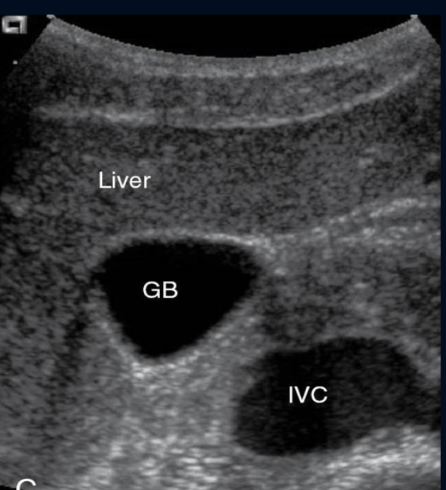

View of GB?

Trv

Neck Post, Fundus Superior